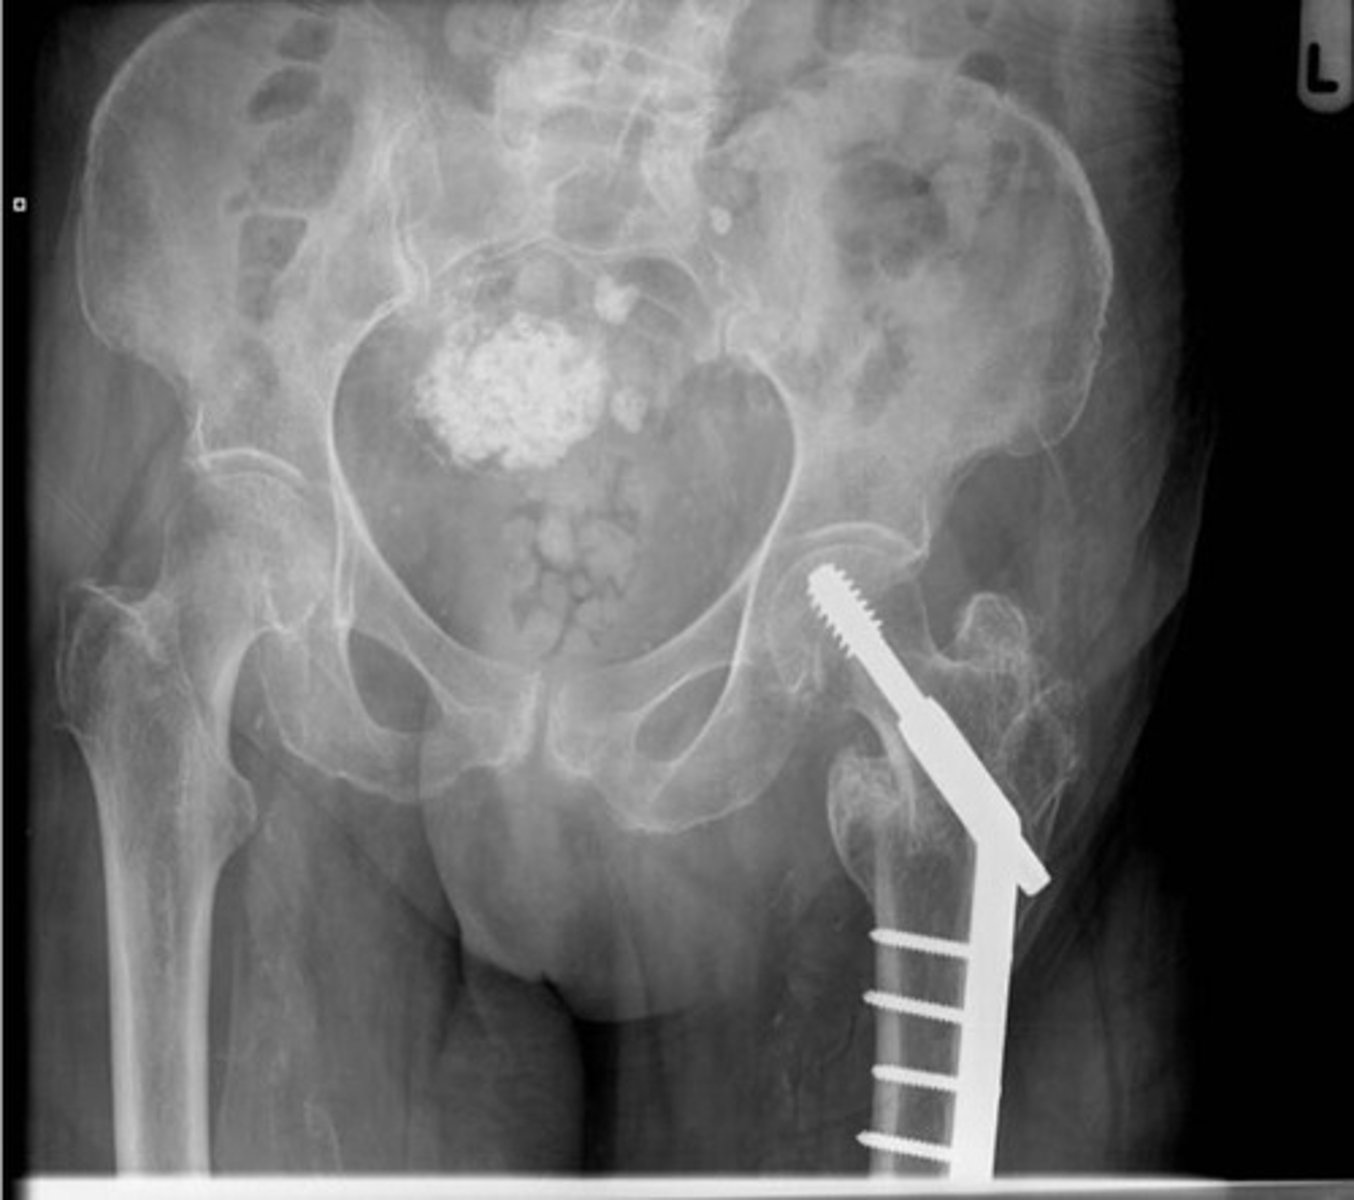

Fibroid

Uterine fibroid/Leiomyoma